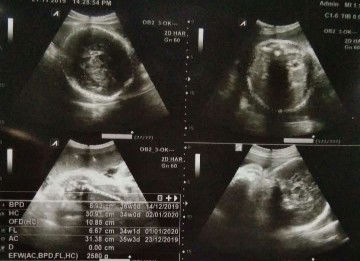

Ada bunda, yg 34w 35w ituloh

Lah itu 34w0d apa?